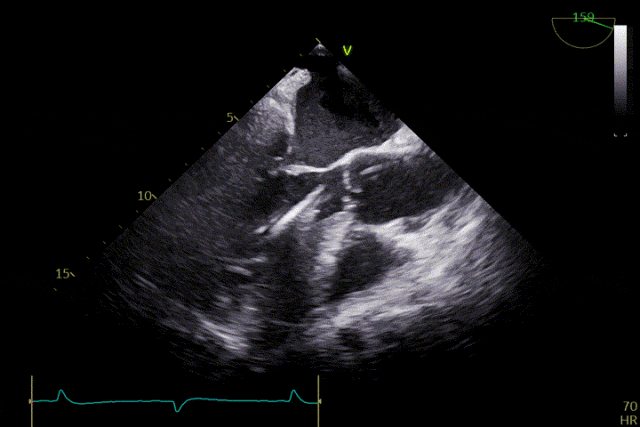

術前超聲

患者主動脈瓣重度反流得到糾正,術後無反流、無瓣周漏。術後心臟超聲顯示人工生物瓣啟閉功能良好,平均跨瓣壓差2 mmHg,血流速度正常。患者恢復情況良好,心功能較術前明顯改善。